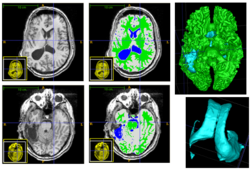

We conducted experiments with the application of the ABC tool to multi-modal image data of 5 TBI cases provided by DBP partner UCLA. The tool includes co-registration of multiple modalities via mutual-information linear registration, and a nonlinear registration (high-deformable fluid registration) of a probabilistic normative atlas for segmentation of healthy tissue. The following results show feasibility of multi-modal registration and segmentation of normal tissue. Pathology is currently segmented via postprocessing using 3D user-supervised level-set evolution.

Case 1: Segmentation of 5channel TBI data with ABC. Lesions and ventricles segmented with additional 3D level-set segmentation.

Case 2: Segmentation of 5channel TBI data with ABC. Lesions and ventricles segmented with additional 3D level-set segmentation.

Case 3: Segmentation of 5channel TBI data with ABC. Lesions and ventricles segmented with additional 3D level-set segmentation.